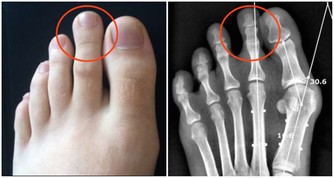

住在中國浙江的一對夫妻,因為工作繁忙的關係而沒時間陪伴10歲的女兒。於是他們買了一隻手機給女兒在無聊時可以打發時間。但有天女兒玩手機玩到一半,聽到媽媽呼喚而抬頭,卻聽到「喀擦」一聲,而且無法動彈,經過醫生的診斷為「頸椎錯位」。

醫生表示,小女孩的頸椎第一、二、三椎向前錯位,「我從醫30多年,第一次碰到這麼嚴重的頸椎病發生在這麼小的孩子身上!」